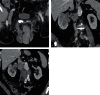

Fig. 4

A. Computed tomography: a 70-year-old patient with varicocele, with larger varicocele on the right (arrows). B. A large right renal cell carcinoma (RCC) with lymph node metastases. C. A tumor plug entering the inferior vena cava and filling nearly its entire cross-section